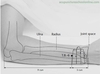

Lu-5

Li-11

Li-15

Ht-1

Ht-3